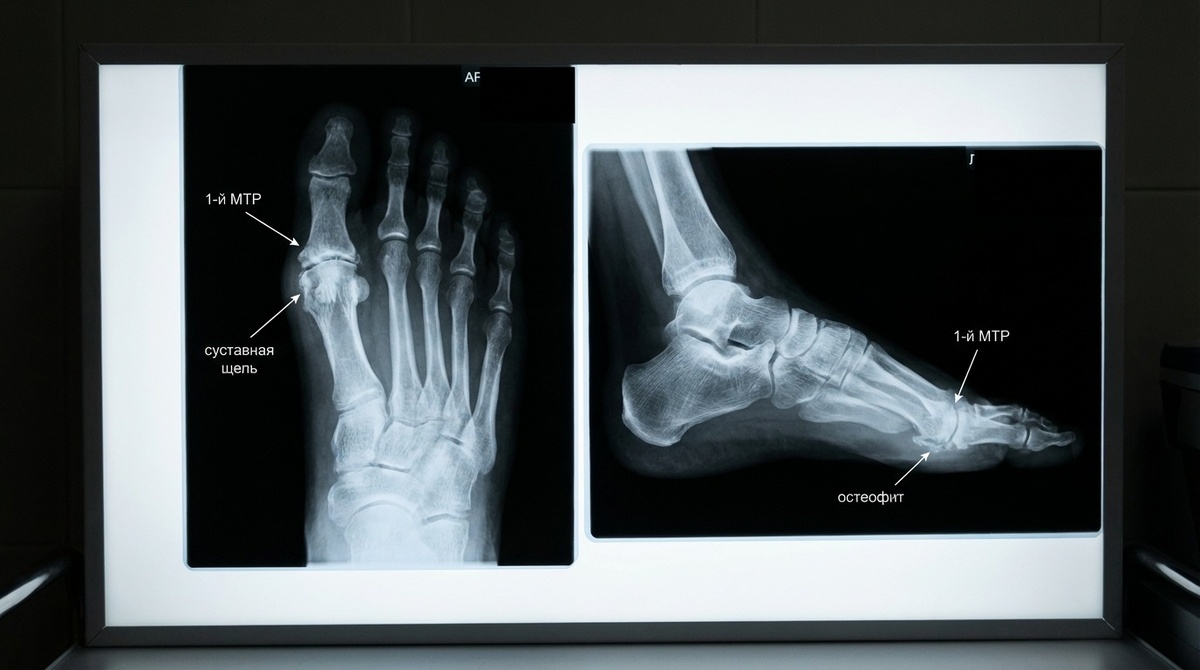

Хрящ истончается, суставная щель сужается, сверху формируются костные разрастания, и палец превращается в жёсткий «шарнир».

Диагностика: что нужно для точного плана лечения

Обычно достаточно:

• осмотра;

• рентгена стопы под нагрузкой в нескольких проекциях.

По снимкам видно степень износа сустава, по осмотру — реальные градусы движения.

МРТ требуется редко — в спорных случаях или при подозрении на локальные повреждения хряща.